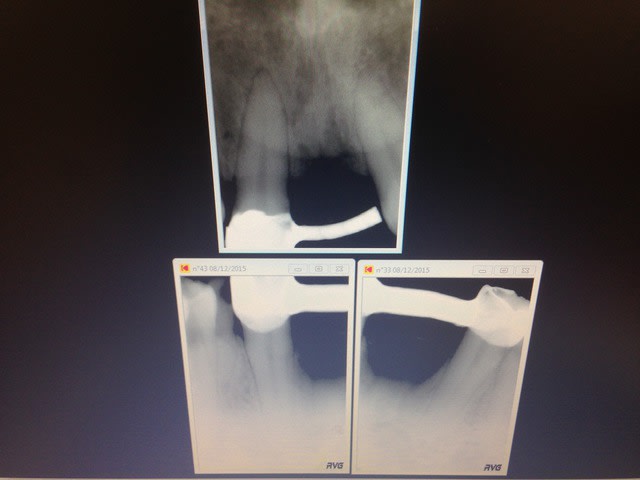

endo ...?

implanto....?

made in france en tout cas

c'est bon les échanges entre pays, on progresse

Img 0186 x9vjj0 - Eugenol

Img 0187 d6lde1 - Eugenol